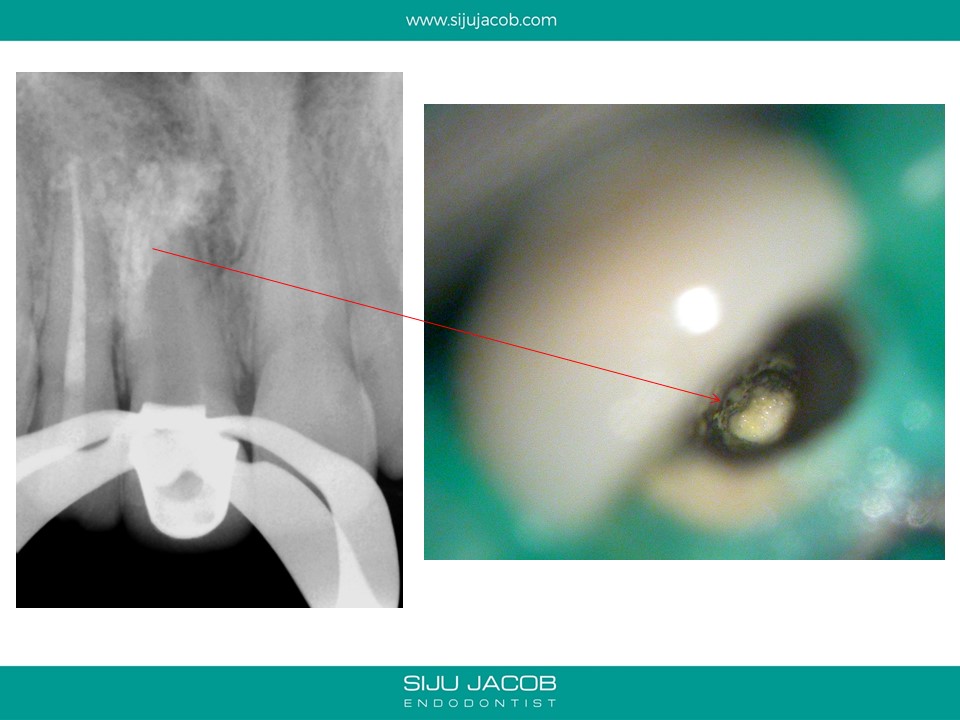

This patient presented with a large lesion associated with a previously endo treated central Incisor with a open apex. The adjacent lateral tested non-vital. I did Endo on the lateral incisor. In the central, I decided to pack Calcium hydroxide till the lesion shrank in size before obturating with MTA. The plan was to keep the original crown in place till there was some evidence of bone fill. The patient disappeared for two years and came back with the lesion completely healed and a solid barrier formed apically through Apexification. I obturated with Gutta percha (No MTA needed) and Advised new crown